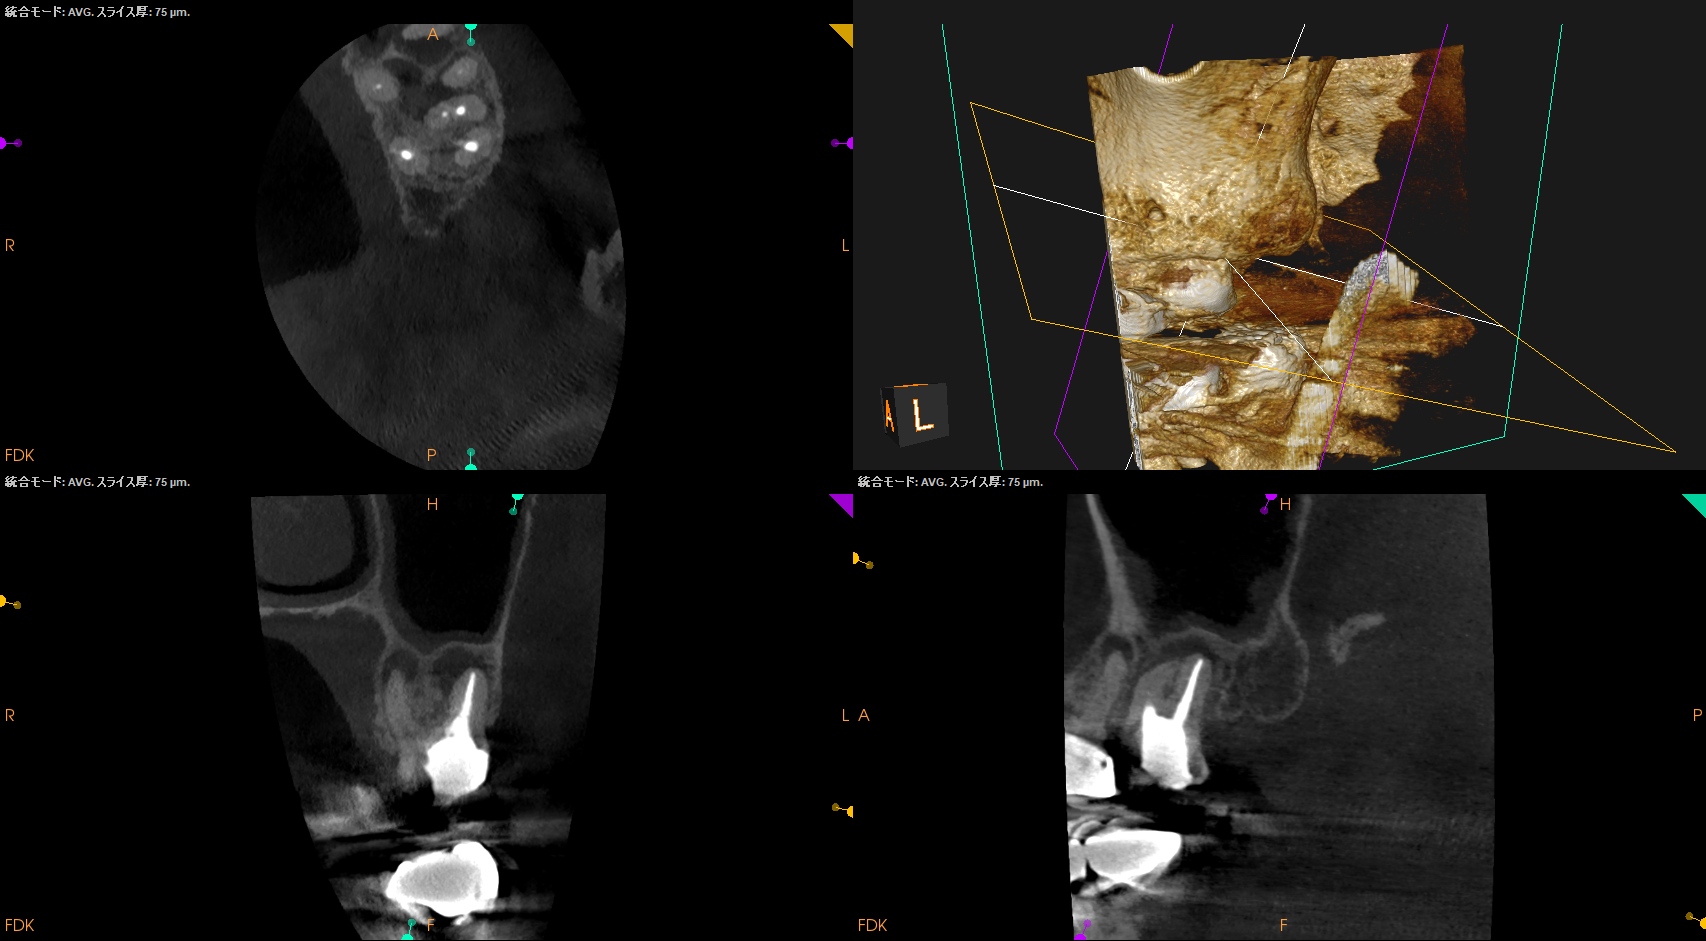

術後のPA, CBCTは以下である。

MB1

MB2

DB

P

問題はないだろう。